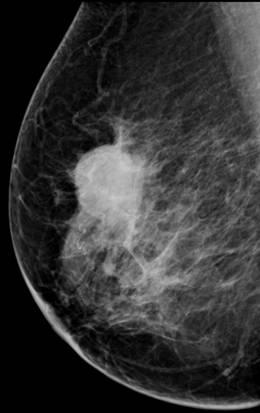

Ung thư vú

» Thông tin: Nữ giới – 76 tuổi.

» Lâm sàng: Khối tuyến vú.